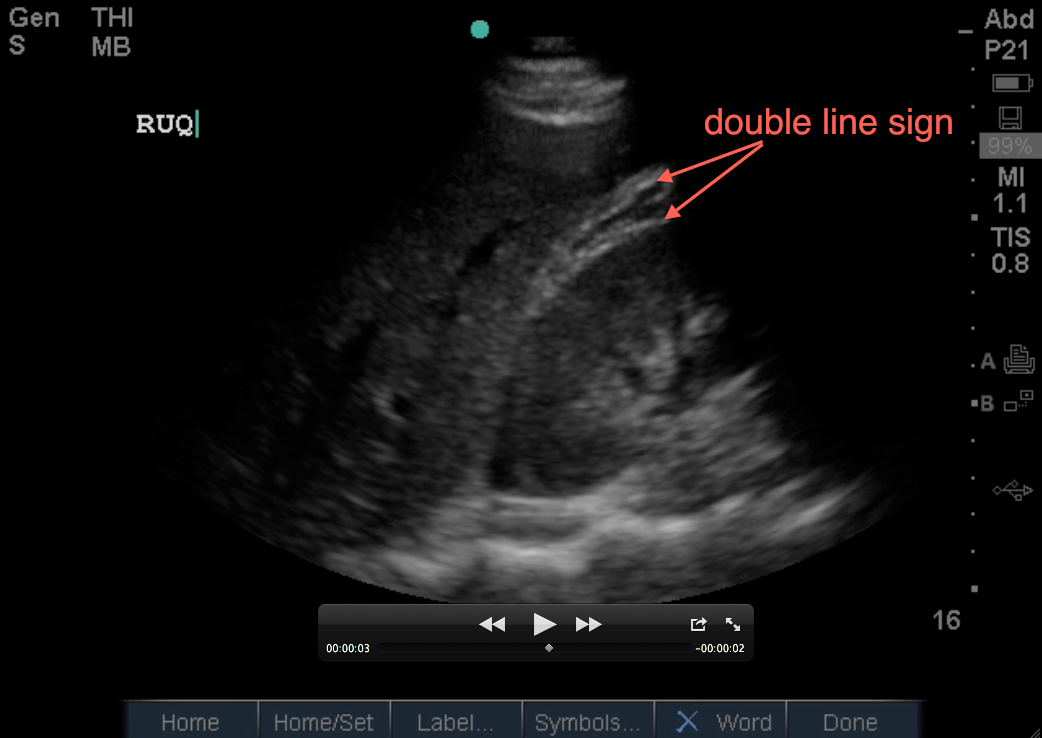

4. Perinephric fat surrounds the kidney in varying amounts depending on the patient. It is echogenic (with shades of gray), but hypoechoic (less bright) than liver and can be mistaken for free fluid. Keep in mind it doesnt move, it is NOT anechoic, and does not appear to be free floating like fluid would be. There’s also a bright line on its edge that doesn’t exist if it were free fluid. Its called the double line sign (one bright line being the outer kidney, the other being the outer edge of the fat). This double line sign helps differentiate it from free fluid as free fluid will not have a double line present.